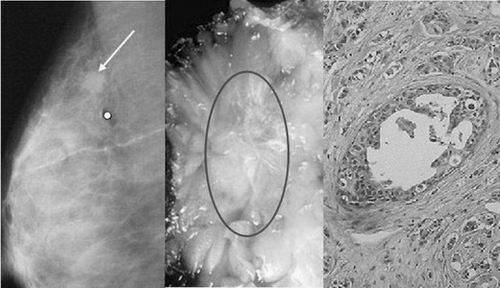

乳腺肿瘤切片图

使用与乳腺肿瘤组织电导率和介电常数相近似的琼脂胶体“SIA”(沈阳自动化所缩写)作为实验样本的微波热声图像重建结果。

近日,由星天地娱乐城官网 沈阳自动化研究所雷达系统研究与应用技术重点实验室研究开发的用于乳腺肿瘤早期检测的微波热声医疗平台取得新进展。

临床实践证明,早期发现的乳腺癌(肿瘤直径<2cm)治愈率高达98%以上,因此发现一个早期乳腺癌对患者的意义远大于目前任何治疗方案。

乳腺肿瘤早期检测微波热声医疗平台克服了常规检测方法低分辨率、低对比度、存在电离辐射等问题,利用不同生物组织在微波激励下介电常数和电导率的差异响应为指导,实现对小型乳腺肿瘤(<0.5cm)的有效检测。

同时,该平台具有安全、舒适、低成本、易于临床诊断操作等特点,有望成为安全实用的早期乳腺癌常规或者辅助检测手段。

目前,该平台在微波热声系统设计、传感器阵列布局设计优化、定量微波热声层析成像理论与方法、多维影像重建等关键技术均有突破性进展,现已成功用于小白鼠体内小型肿瘤(<1cm)的检测,并取得良好效果。